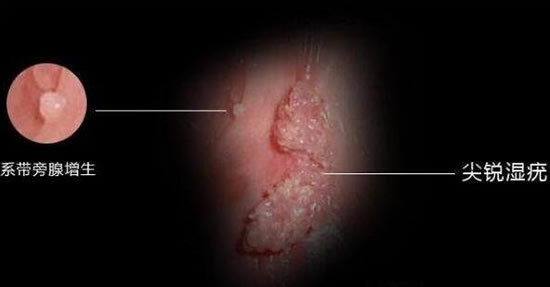

hpv感染的外在症状图解

一、身上有菜花状的疣体

如果感染了低危型的HPV,会导致手臂上。大腿上或是隐私部位出现菜花状或鸡冠状的疣体,就像是个小肉揪,淡粉色或是暗红色的,会不断增大,像是过敏的症状,但又不是,如果HPV没有彻底转阴,这种小肉揪是不会消失的。

1、皮肤上长出疣体

绝大部分低危HPV感染都会在皮肤导致疣体的出现,对于妇科如果在生殖器出现疣体,最常见的就是HPV6型、HPV11型感染,这两种人类乳头瘤病毒感染往往会导致生殖器的尖锐湿疣。另外,hpv病毒还会长出皮肤上的疣,包括扁平疣、生殖器官尖锐湿疣、寻常疣、丝状疣等!大家要引起重视!